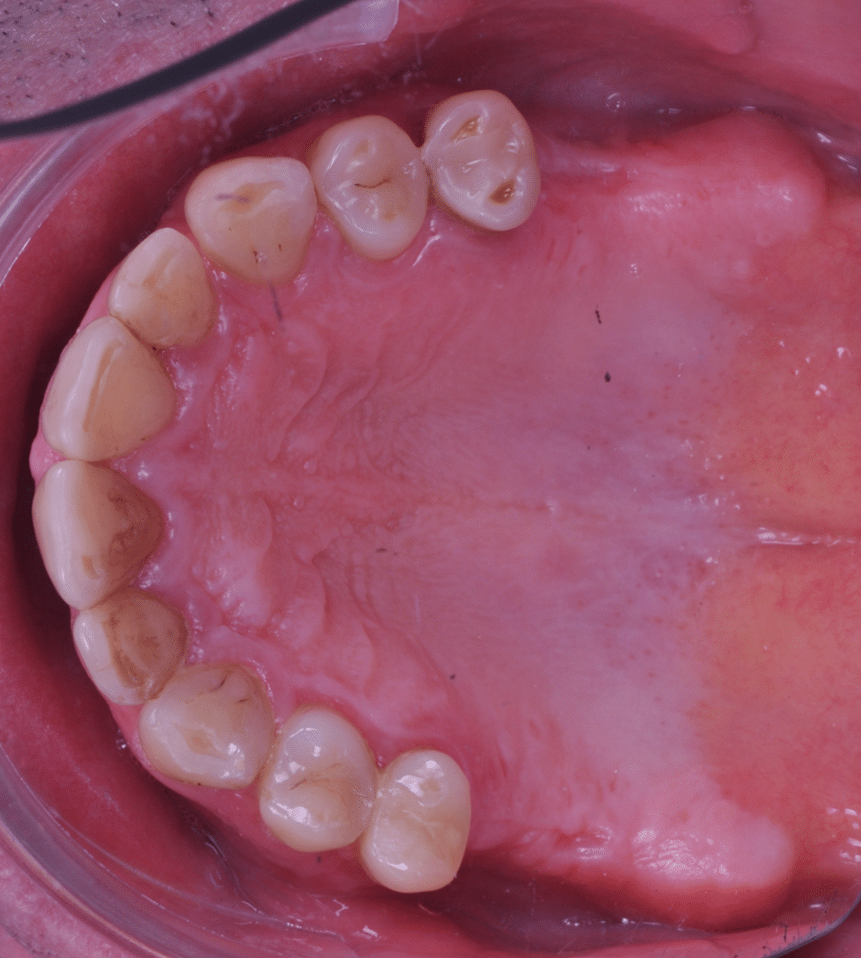

Împreună cu pacientul, am optat pentru inserarea implantelor cu ajutorul ghidului chirurgical pentru a plasa implantul în poziția protetică ideală și pentru a permite realizarea coroanelor insurubate pe implant. A fost efectuată scanarea digitală a arcadelor și a ocluziei pacientului, iar împreună cu tehnicianul radiolog de la DigiRay a fost suprapus fișierul .stl al amprentei digitale peste fișierul .dcm de la CBCT, utilizând software-ul 3Shape.

S-a planificat individual poziția și axul de inserție al fiecărui implant.